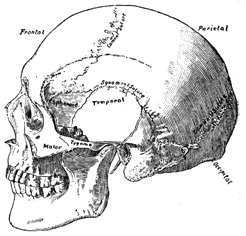

Chapter II—Structure of the Brain.

of the brain in the head, illustrated and described—The cerebrum,

cerebellum, and tentorium—Interior view of the base of the skull—Bones

of the head illustrated—Division of the brain into lobes

Let us take an exterior view by

removing one half of the skull from

the right side of the head. This

enables us to see that the front

portion of the brain rests above the

sockets of the eyes, coming down in

the centre as low as the root of the

nose, but a little higher exteriorly.

When we touch the forehead just